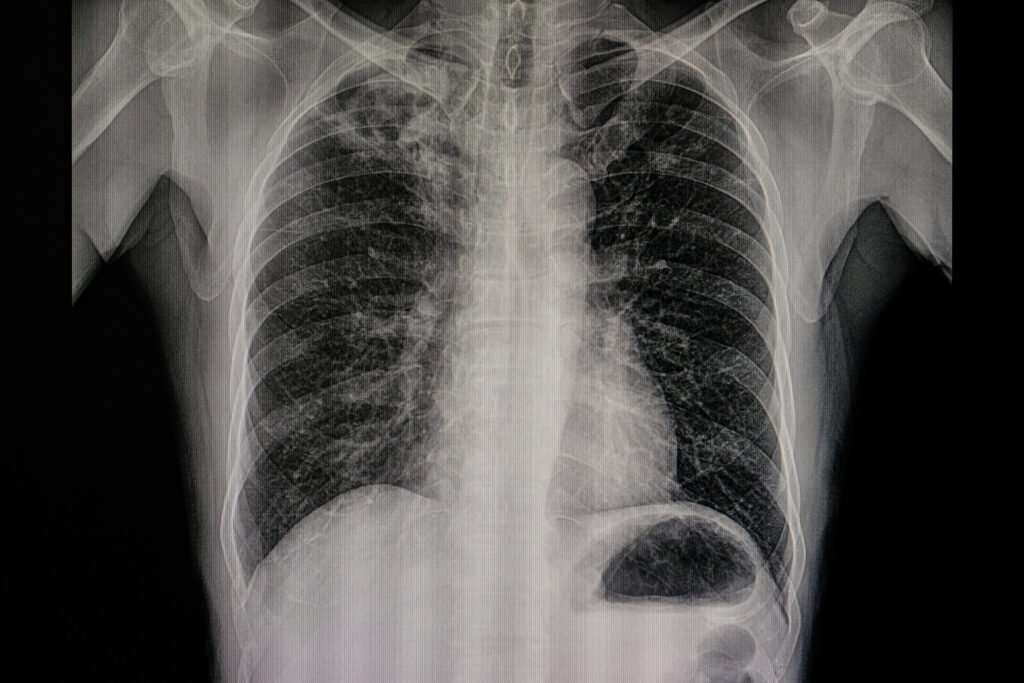

Cancer frequently stays undiagnosed until it is advanced. Many cancer signs and symptoms, such as chronic fatigue, cough, discomfort, or loss of appetite, might be dismissed as minor inconveniences rather than indicators of a severe medical problem. A full-body scan can provide you with peace of mind. Alternatively, if it assists practitioners in detecting irregularities […]